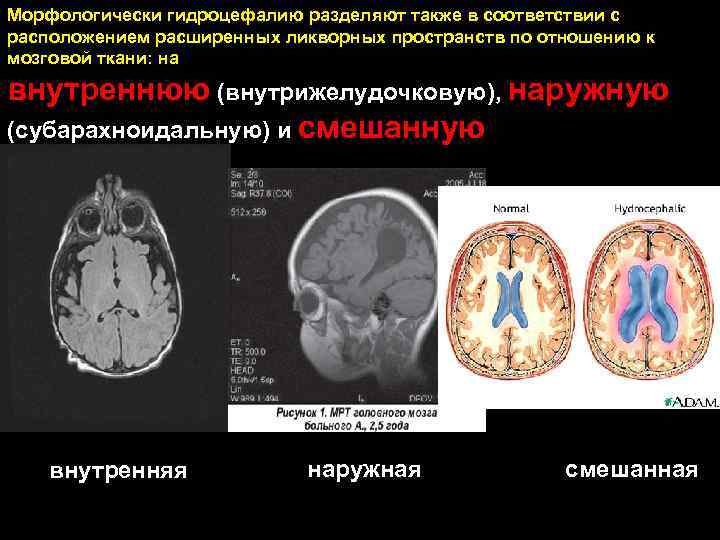

Морфологически гидроцефалию разделяют также в соответствии с расположением расширенных ликворных пространств по отношению к мозговой ткани: на внутреннюю (внутрижелудочковую), наружную (субарахноидальную) и смешанную внутренняя наружная смешанная 91